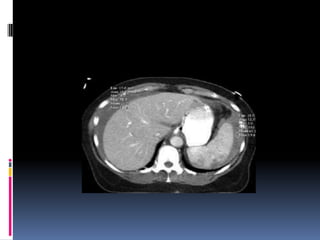

INJURIA PANCREÁTICA  Resultade la compresión de la glándula contra la columna vertebral  Manubrio de bicicleta  Clínica y laboratorio inicialmente inespecíficos

 Signos indirectosde lesión traumática  Agrandamiento difuso  Grasa peripancreática “sucia”  Líquido periglandular  Engrosamiento fascia pararrenal anterior